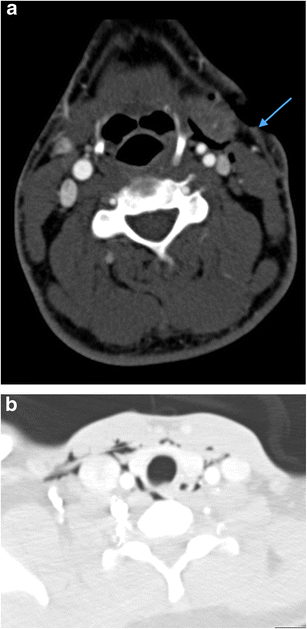

a Axial image of MDCTA performed on a 33-year-old man who sustained a stab injury to left zone 2. The platysma has been breached (arrow) and there is soft tissue emphysema in the deep cervical fascia surrounding the left carotid sheath. No major vascular injury or upper aerodigestive tract penetration was present. There was no pneumothorax. b Axial image of MDCTA through zone 1 on lung-window settings of a different patient who sustained left zone 2 penetrating knife injury with breach of platysma (image not shown). Diffuse soft tissue emphysema is noted in the deep cervical fascia bilaterally in zone 1 despite penetrating wound entry in left zone 2. This can be a common finding in penetrating neck injury where platysma has been breached even in the absence of perforation of the upper aerodigestive tract or pneumothorax. Nevertheless, penetration of the laryngopharynx should be further excluded where clinical and radiological suspicion is high. (Contrast swallow was negative in this patient)